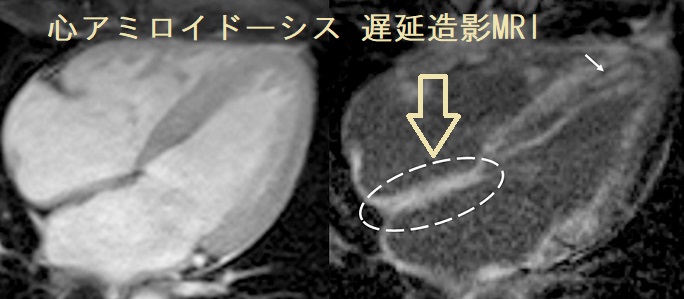

- 心アミロイドーシス;心臓の間質にアミロイド線維が沈着する二次性心筋症で不整脈・心肥大・左室拡張障害による心不全。心電図で低電位差、心エコーで心筋肥厚・エコー輝度増加、心筋生検が診断に有用。

甲状腺アミロイドーシスによる甲状腺機能低下症に心アミロイドーシスを合併すれば、徐脈・心不全が相乗効果で増悪します。心アミロイドーシスの生命予後は4カ月です。

トランスサイレチン遺伝子変異による心アミロイドーシスはピロリン酸シンチグラフィー(201TlCl+99mTc-PYP)で心筋全体に集積を認めるのが特徴。[Amyloid. 2003 Dec;10(4):229-39.]